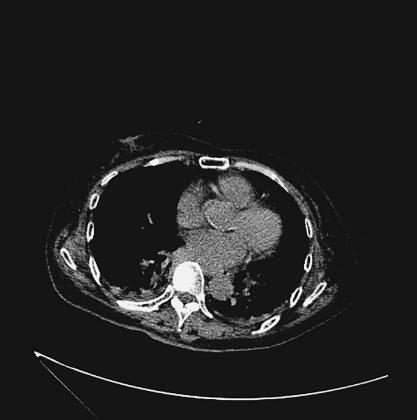

辅助检查:胸、腹部CT示双下肺炎(图1、图2)。心电图示窦性心动过速。血常规:WBC 29.05×109/L,N 88.0%;血气分析:pH 7.383,PO2 54.3mmHg,PCO2 24.9mmHg,SPO2 87.0%;心肌钙蛋白-I 14.3μg/L;生化:总蛋白39g/L,白蛋白19g/L,谷丙转氨酶665U/L,谷草转氨酶582U/L,总胆红素22.0μmol/L,B型脑钠肽1863pg/ml,尿素氮11.8mmol/L,葡萄糖10.9mmol/L,血浆乳酸4.3mmol/L,肌酸激酶512U/L,心肌肌酸激酶42U/L,C-反应蛋白197.0mg/L;糖化血红蛋白14.3%;多次痰培养及血培养均未培养出致病菌。

图2 入院时胸部CT示双肺炎症(纵隔窗)